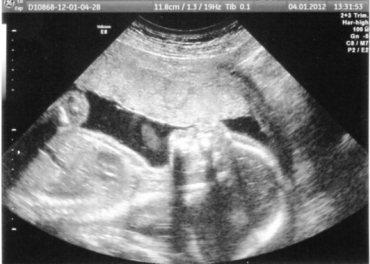

tak už jsme doma ... na UZ vše v normě, paní doktorka byla taková nějaká nepříjemná, nějak extra se k tomu všemu nevyjadřovala, docela protivně se mě ptala, jestli teda jako fakt nechci jít na ten odběr vody a že mi ho KLIDNĚ udělají i dnes tam u nich, tak jsem řekla, že nechci, že jdu zítra u nás v nemocnici, napsala asi 5 řádků do zprávy - vůbec nerozepsala funkci a stav jednotlivých orgánů, jak se to dělá u nás ve špitále, dle hlavičky jsme 21+5, dle stehenní kosti 20+5, tak z toho prostě udělala 21.tt, TP nijak neřešila, jestli zůstává stejný ... prostě nevím, už tam nikdy nepojedu ... a malý samozřejmě moc nespolupracoval, hlavu měl schovanou dole, tak máme jen takovou mizernou fotečku,ani 3D bešlo udělat ...